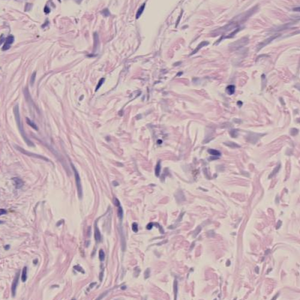

Crowded between the collagen fibers are rows of fibroblasts fiber-forming cells that generate the fibers. Tendons transmit forces generated by muscles to move joints. The best dense regular connective tissue examples are the tendons and ligaments. Tendon injuries most commonly occur in the hand.

Dense irregular connective tissue has collagen fibers randomly interwoven forming a three. Bone and cartilage are examples of supportive connective tissue that give the body shape and strength while also protecting soft tissues. Dense connective tissue forms strong rope-like structures such as tendons and. Dense connective tissue is dense because of the high proportion of fibers that run parallel to each other.

Dense regular tissue is found in tendons ligaments and muscle fascia. Tendons are dense connective tissues that connect muscle to bone. Collagen fibers are found in rows between several antiparallel bundles of fibers in dense regular connective tissues. Connective tissue in tendons and ligaments are examples of dense regular connective tissue.